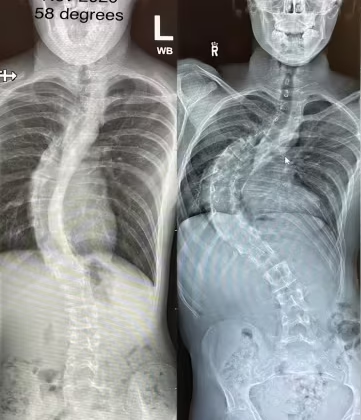

فشل الحزام يعني أنّ زاوية الاعوجاج (Cobb angle) لم تتحسن أو ازدادت بالرغم من الالتزام بارتدائه. الهدف الأساسي للحزام هو تقليل الانحناء، لذلك يعتبر فاشلًا عندما:

لا يحقق نسبة التصحيح المطلوبة داخل الحزام (In-brace correction).

1) عدم تحقيق التصحيح المطلوب على الأشعة داخل الحزام

40–60% تصحيحًا على الأقل داخل الحزام في أغلب الحالات المراهقية.

2) استمرار زيادة زاوية الاعوجاج مع المتابعة

حتى لو كان الطفل ملتزمًا بارتداء الحزام، إذا ارتفع الانحناء أكثر من 5 درجات خلال 6 أشهر فهذا مؤشر واضح على فشل الحزام.

إجراء أشعة داخل الحزام بعد 2–4 أسابيع من التسليم